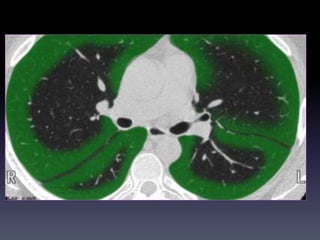

CAÂY PHEÁ QUAÛN VAØ PHAÂN

THUØY PHOÅI

+CT cho chi tieát giaûi phaãu toát raát nhieàu so

vôùi X quang qui öôùc

+Phaân tích hình aûnh CT

-Caây pheá quaûn

-Phaân thuøy phoåi

-Raõnh maøng phoåi